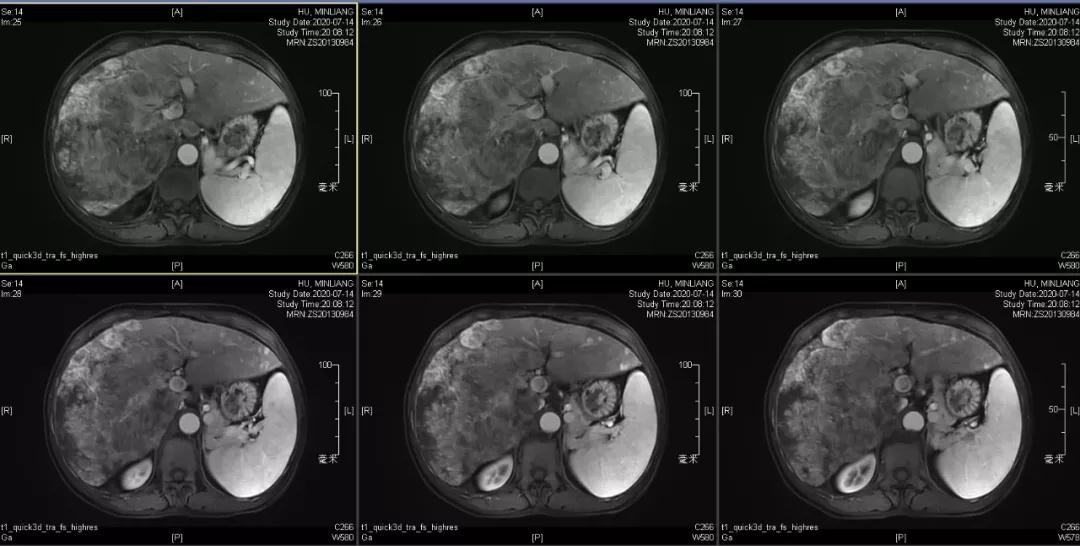

肿瘤学评估(用药后2个月对比6个月):肝内主瘤明显缩小,动脉期强化降低;子灶消失;门脉右支癌栓明显缩小坏死;肺转移灶缩小,大部分消失。

2020-09-15

2021-01-25

Δ治疗过程中病灶影像学变化

用药2个月后:要不要转化切除?考虑到患者伴有肺转移,决定继续用药观察,若肺转移继续稳定,可考虑转化切除,抗病毒治疗建议改TAF治疗。

用药6个月后:肝脏病灶明显缩小,子灶消失,仅有少量动脉期强化;肺转移单个持续缩小稳定,PET CT活性弱;HBV DNA 转阴;可考虑转化切除。